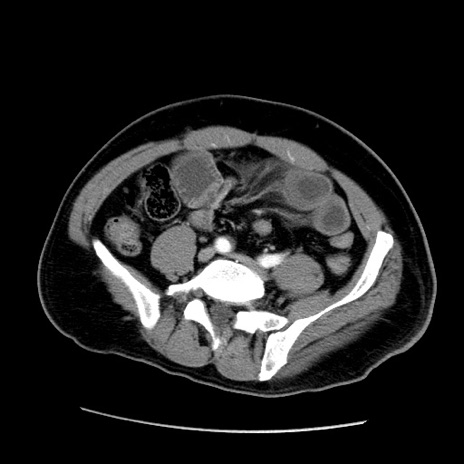

冠状断像

【症例】50歳代男性

【主訴】腹痛

【現病歴】AVMからの被殻出血のため回復期リハ病棟入院中。 本日午後3時頃急に下腹部痛が出現した。

【既往歴】AVM、被殻出血、虫垂炎、高血圧

【身体所見】意識晴明、左半身不全麻痺、会話の理解は良好、36.5°C、腹部:膨隆、全体に板状硬、下腹部正中に圧痛点あり、反跳痛-、筋性防御不明、右下腹部にope scar

【データ】WBC 9400、CRP 0.06